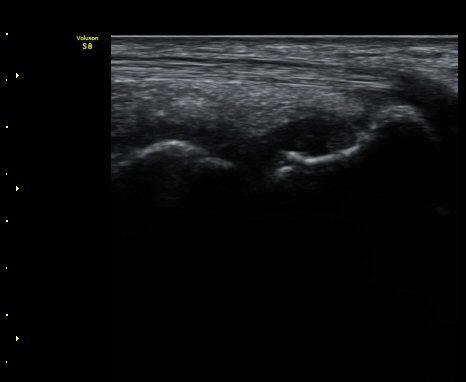

ÃÊÀ½ÆÄ °Ë»ç

ÁÖ»ó°ñ ¼±»ó°ñÀýÀº ´Ü¼ø¹æ»ç¼± ÃÔ¿µ ½Ã È®ÀεÇÁö ¾ÊÀº °æ¿ì°¡ ¸¹Àºµ¥ ÀÌ ¶§ ÃÊÀ½ÆÄ

°Ë»ç°¡ ÁÖ»ó°ñ °ñÀý Áø´Ü¿¡ ¸Å¿ì À¯¿ëÇÏ´Ù. ±×·¯¹Ç·Î ¼Õ¸ñ ´ÙÄ£ ÈÄ Áö¼ÓÀûÀÎ ÅëÁõÀ»

È£¼ÒÇϰí ÁÖ»ó°ñ ºÎÀ§ ¾ÐÅëÀ» º¸ÀÌ´Â °æ¿ì ÃÊÀ½ÆÄ°Ë»ç¸¦ ½ÃÇàÇÏ¿© ÁÖ»ó°ñ °ñÀý ¿©ºÎ¸¦

È®ÀÎÇØ¾ß ÇÑ´Ù.

ÃÊÀ½ÆÄ°Ë»ç¸¦ ½ÃÇàÇÒ ¼ö ¾ø´Â °æ¿ì´Â ÄÄÇ»ÅÍ ÃÔ¿µ°Ë»ç¸¦ ÁÖ»ó°ñ °ñÀýÀ» È®ÁøÇÒ ¼ö ÀÖ´Ù.